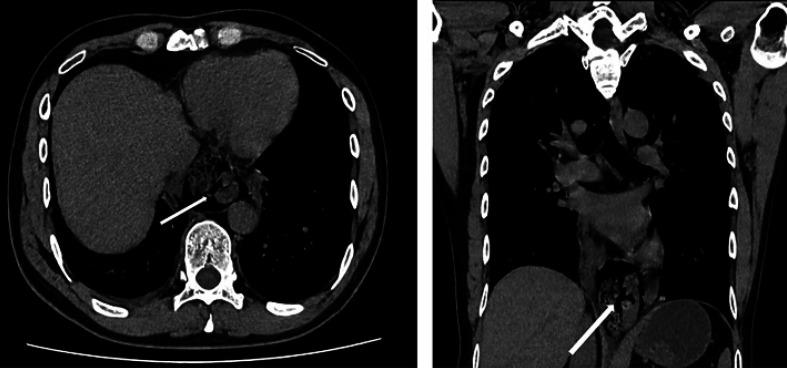

Spontaneous esophageal perforation in Boerhaave's syndrome results in significant morbidity and mortality. The gold standard treatment for this disease is thoracotomy and laparotomy because it can be a life-saving procedure that can be performed in emergencies; however, minimally invasive surgery has recently been reported. This report describes three cases of Boerhaave's syndrome that were treated using laparoscopic transhiatal suture and omental patch. One patient recovered uneventfully and was discharged from the hospital after 12 days. The other 2 patients had postoperative complications, such as minor leakage and remnant abscess (Clavien-Dindo Grade II), but were discharged from the hospital after 17 days and 30 days, respectively. In the case of Boerhaave's syndrome with localized mediastinal collections, a good clinical course can be obtained by laparoscopic transhiatal esophageal repair to avoid surgical invasion due to thoracotomy.

博赫哈夫综合征中的自发性食管穿孔会导致严重的发病率和死亡率。该病的金标准治疗方法是开胸手术和剖腹手术,因为这是一种可在紧急情况下实施的挽救生命的手术;然而,最近有关于微创手术的报道。本报告描述了3例采用腹腔镜经裂孔缝合和网膜补片治疗的博赫哈夫综合征病例。1例患者恢复顺利,术后12天出院。另外2例患者出现术后并发症,如轻微渗漏和残余脓肿(Clavien-Dindo二级),但分别于术后17天和30天出院。对于伴有局限性纵隔积液的博赫哈夫综合征,通过腹腔镜经裂孔食管修复术可获得良好的临床病程,以避免开胸手术带来的手术创伤。